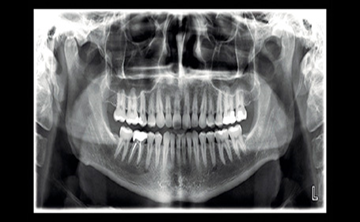

DIGITAL OPG

BEST OPG CENTRE IN PALAKKAD . AT PULSE SCANS .

REDEFINING DENTAL IMAGING

PLANMECA PROMAX SCARA 3 WITH ROMEXIS SOFTWARE - a new benchmark for dental imaging.

The Planmeca ProMax is a complete maxillofacial imaging system, with design and operation principles based on the latest scientific research and technological innovations adressing the most demanding needs of dental fraternity. Planmeca ProMax offers complete dental imaging solutions – in panoramic and cephalometric imaging. Our robotic SCARA technology , for example, offers flexible, precise and complex movements needed for extraoral maxillofacial imaging. Planmeca Romexis - offering the most advanced and versatile software to meet all your extraoral imaging needs. CHILD-FRIENDLY IMAGING: is important to avoid excessive doses when caring for all patients, but low dose imaging should be paid particular attention to when imaging younger patients ( more radiosensitive ). The availability of pediatric imaging capabilities combined with the  Planmeca Ultra Low Dose™  imaging protocol ensure that children do not need to be exposed to excessive patient doses – making the Planmeca imaging ecosystem safe for all patients.We also have a dedicated team of professional radiographers behind the scenes that make a real difference.